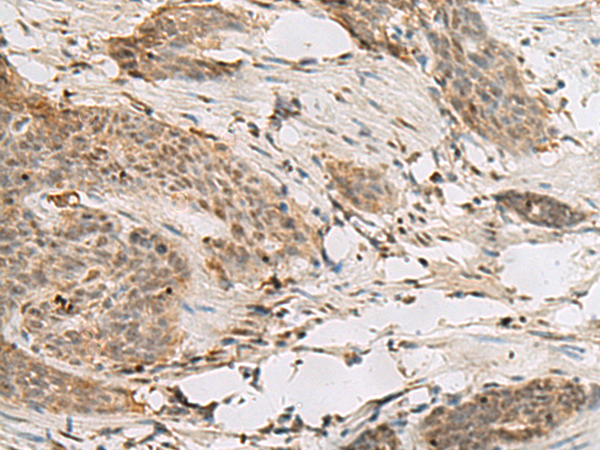

IHC (Immunohistochemistry)

(Immunohistochemistry analysis of paraffin-embedded human breast carcinoma tissue, using Histone H1 (Acetyl-Lys25) Antibody. The picture on the right is blocked with the synthesized peptide.)